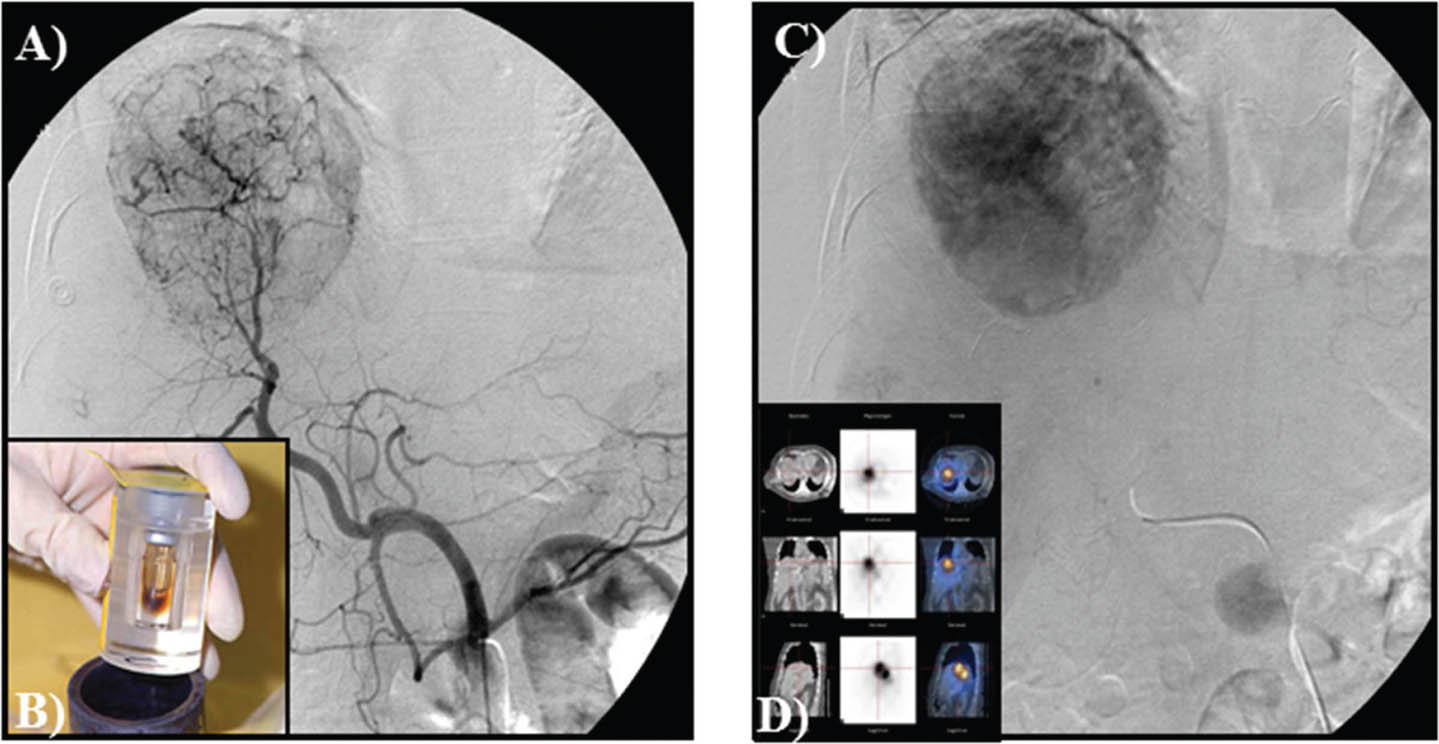

TACE is currently the standard of care for patients with intermediate–stage HCC with preserved liver function (7880). TACE is useful for patients that have a Child-Pugh score A or B with tumor diameter of >4 cm or four or more tumors as well as those with single tumor in which it is challenging to carry out liver resection or locoregional therapies as a result of systemic co-morbidities or anatomical limitations (81). TACE takes advantages of the dual arterial and portal venous liver parenchymal blood supply with preferential arterialization not only in cirrhotic liver but of HCC. It involves the selective arterial embolization with a gelatin mixed with lipiodol (a radiopaque contrast agent) with or without chemotherapy (doxorubicin, cisplatin or mitomycin C), into the tumor’s feeding blood vessel (66). The blockage of the arteries supplying the tumor results in tissue necrosis (Figure 10) (68, 79). In practice, TACE is a recommended therapy for patients with unresectable HCC, nonvascular invasion or disease outside the liver (64). TACE can also be used with drug-eluting beads (DEB-TACE) and evidence exists that patients who are on DEB-TACE treatments for unresectable HCC have better performance in comparison to those on conventional TACE (66). In addition, TACE is being used for the downstaging of tumors in association with systemic therapy or as bridge for transplantation.

Fig 10

Figure 10. Trans-arterial chemoembolization of the liver for hepatocellular carcinoma. A and B. Selective arterial embolization of the vessels feeding the tumor in the liver. C. Tumor visualized by CT scan. The procedure is performed with or without chemotherapy. D and E. After embolization, angiography showed obliteration of feeding vessels with shrinkage of the tumor. F. Follow up CT scan after embolization. Note an increase in patient’s ascites.

Y-90 radioembolization

Y-90 radioembolization is a locoregional technique that involves a catheter-based administration of Y-90 microspheres into the hepatic artery, leading to the delivery of high radiation doses up to 50 to 150 Gy to tumors without affecting the parenchymal cells (Figure 11) (82, 83). This exploits the principle; intrahepatic tumors derive their major blood supply from the hepatic artery rather than the portal vein. Y-90 emits beta radiation with an average energy of 0.9 MeV and a mean penetration range of 2.5 mm (approximately 1,000 cell diameters). The physical half-life of Y-90 is 64.2 hours, and it decays to stable Zirconium-90 (82, 83). Microspheres (embedded with Y-90) are of varying sizes, ranging from 20 to 60 microns. In the US, the common available forms of Y-90 include the Y-90 tagged glass (TheraSphere) and resin (SIR-Spheres) microspheres (82). The main difference between Y-90 radioembolization and TACE is that Y-90 microspheres are smaller than TACE particles (20-30 microns compared to 200-500 microns). Therefore, TACE gives a more significant embolic effect in comparison to Y-90 radioembolization. However, the main mechanism of action of Y-90 is related to radiation effect and not the embolic occlusion of the blood supply to the cancer cells, thereby making it a more effective therapy (82, 83).

Fig 11

Figure 11. Y-90 embolization for hepatocellular carcinoma. A. Selective angiography of the liver and detection with obliteration of systemic shunts is performed. B, C and D. Micro-spheres then are embolized to the liver with no vessel occlusion.